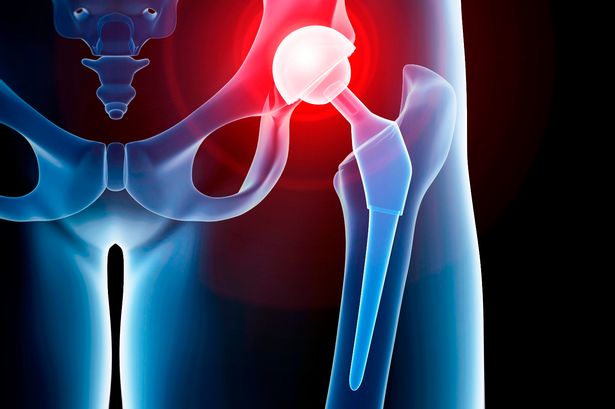

Hip replacements surgery can be performed traditionally or by using what is considered a minimally-invasive technique. The main difference between the two procedures is the size of the incision. During standard hip replacement surgery, you are given general anesthesia to relax your muscles and put you into temporary deep sleep. This will prevent you from feeling any pain during the surgery or have any awareness of the procedure. A Spinal Anesthetic may be given to help prevent pain as an alternative. The doctor will then make a cut along the side of the hip and move the muscles connected to the top of the thighbone to expose the hip joint. Next, the ball portion of the joint is removed by cutting the thighbone with a saw. Then an artificial joint is attached to the thighbone using either cement or a special material. After surgery a patient can : Play Golf, Climb Stairs, Drive a Car, Sit Crossed Legs.

Indications for Hip replacement are :